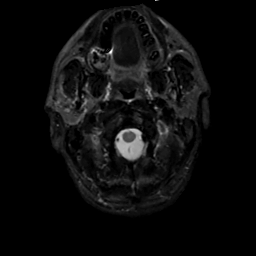

MR Study #1, February 10, 1991 -- Slice #1